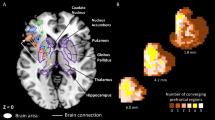

We re-analysed data of stroke patients admitted to the Centre of Neurology at the University of Tübingen. Patients were retrospectively identified in datasets collected in previous studies11,23,36,37,38. All patients had a first-ever unilateral cerebral stroke to the right hemisphere confirmed by CT or MRI imaging. Patients with a medical history of a neurological or psychiatric disease that could interfere with the neuropsychological assessment as well as patients with diffuse lesions or tumours were excluded. Selection criteria were: (1) stroke affecting the basal ganglia or the thalamus, (2) no visible damage to cortical areas, and (3) no or only minor damage to white matter (average white matter lesion volume was 1.9 ± 2.25 cm³; range = 0.0–10.8 cm³). These criteria were first liberally checked by an automated search across available datasets by reference to the AICHA brain atlas39. A second, visual evaluation of the neuroimaging of potentially suitable datasets resulted in a sample of 43 stroke patients. Demographic and clinical data are shown in Table 1; lesion topographies in Fig. 1. The original studies that collected clinical data as well as the re-analysis of the data were approved by the local ethics board and have been performed in accordance with the revised Declaration of Helsinki. Patients or their relatives gave their informed consent for participation in the study.

We found a lesion load in at least one of the four fibre tracts in 28 out of 43 patients. This was the case for 12 out of 15 patients with spatial neglect and 12 out of 29 patients without spatial neglect. This ratio was significantly larger in patients with spatial neglect (χ2(1, N = 43) = 3.88; p = 0.049). For all four fibre tracts, at least some patients with a lesion load were identified ranging from 13 to 23 patients (Fig. 5). The rank correlation between the mean CoC score and the lesion load in each fibre tract ranged from τ = 0.20 to 0.27. However, while the correlation coefficients were significant for all fibres except the SLF, no results remained significant after Bonferroni correction. The correlation between the total lesion load across the four fibre tracts and the mean CoC was highly significant (τ = 0.31; p = 0.005; Fig. 5), the correlation remained significant when only patients with damage to the basal ganglia were included (τ = 0.32; p = 0.023), but not for the thalamic stroke patient sample (τ = 0.24; p = 0.27). In a control analysis, we looked at the weighted lesion load that incorporated the full probabilistic information of the fibre tract atlas. This analysis closely replicated the correlation between lesion load and mean CoC (τ = 0.32; p = 0.003). The out-of-sample prediction accuracy of the random forest classifier was highly significant above chance (p = 0.0048; AUC = 0.76), meaning that the multivariate consideration of tract-wise disconnection can predict spatial neglect in subcortical stroke.